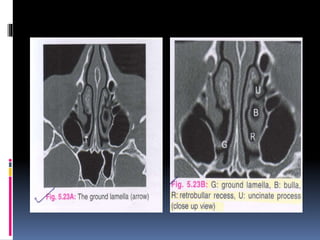

 The middle turbinate is attached to lamina

papyracea by its ground lamella.This

lamella separates anterior ethmoid cells

from posterior ethmoid cells.

 The middleturbinate is attached to lamina papyracea by its ground lamella.This lamella separates anterior ethmoid cells from posterior ethmoid cells.